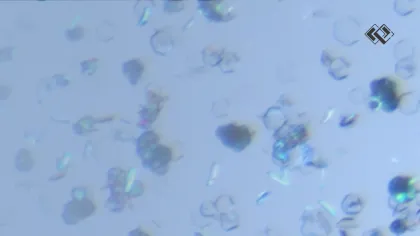

In the world of drug development, PROTACs (Proteolysis Targeting Chimeras) are notoriously difficult to crystallize. Their high molecular weight, inherent flexibility, and complex surface area often leave traditional screening methods coming up empty. However, recent research combined with industry expertise proves that the right screening strategy can fundamentally change the equation.

A recent JACS paper—"Crystallizing the Uncrystallizable: Insights from Extensive Screening of PROTACs" (Screen et al., 2025)—provides a sobering look at these challenges. A collaborative team from Durham University, AstraZeneca, the University of Southampton, and Newcastle University conducted an exhaustive study on a PROTAC molecule designated "AZ1."